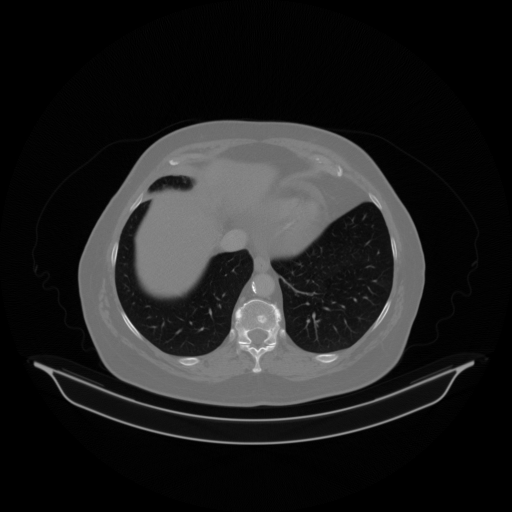

Reconstructed NATIVE CT scan (cycle consistency)

No window - Raw intensity values

Lung window (WL -600, WW 1500 β†’ Low βˆ’1350, High +150)

Mediastinum window (WL 40, WW 400 β†’ Low βˆ’160, High +240)